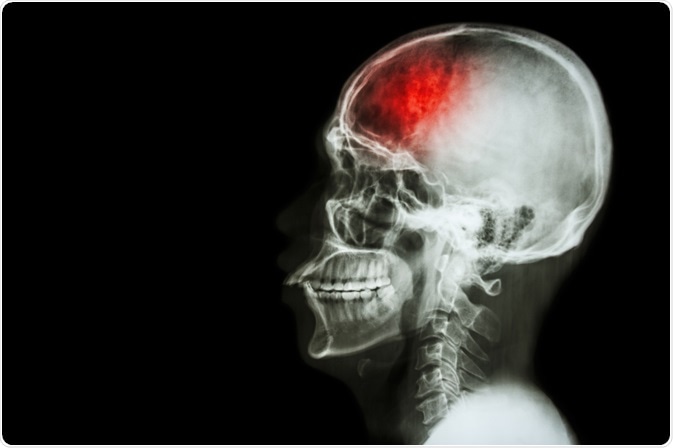

Head trauma refers to any damage to the scalp, skull or brain caused by injury. Head injury may be classified in various different ways according to the type of injury, which structures in the head are damaged or how severe the trauma is.

head traumaImage Credit: Puwadol Jaturawutthichai / Shutterstock.com